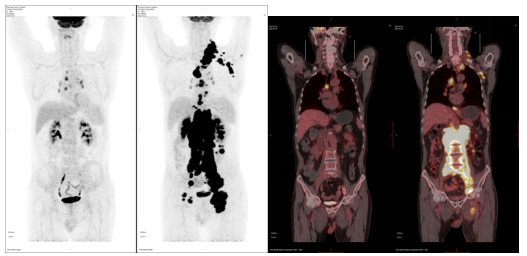

PET-CT是目前对癌症最敏感的成像和先进的诊断方法之一,是精准的分子成像设备。检查前患者注射微量的放射性标记的放射性药物,药物在人体内的分布被PET设备追踪。结合计算机断层扫描(CT),提供身体内部结构的解剖图像。当前,常用的肿瘤诊断放射性药物是利用肿瘤细胞普遍大量消耗糖的原理,给患者注射18F标记的葡萄糖(18F-FDG)作为示踪剂,诊断肿瘤和其他疾病。世界上,用于肿瘤诊断、分期、监测复发和分子分型的其他分子显像剂也在开发并有望快速推向临床转化。

PET-CT清晰直观地显示肿瘤治疗前后全身病灶对比